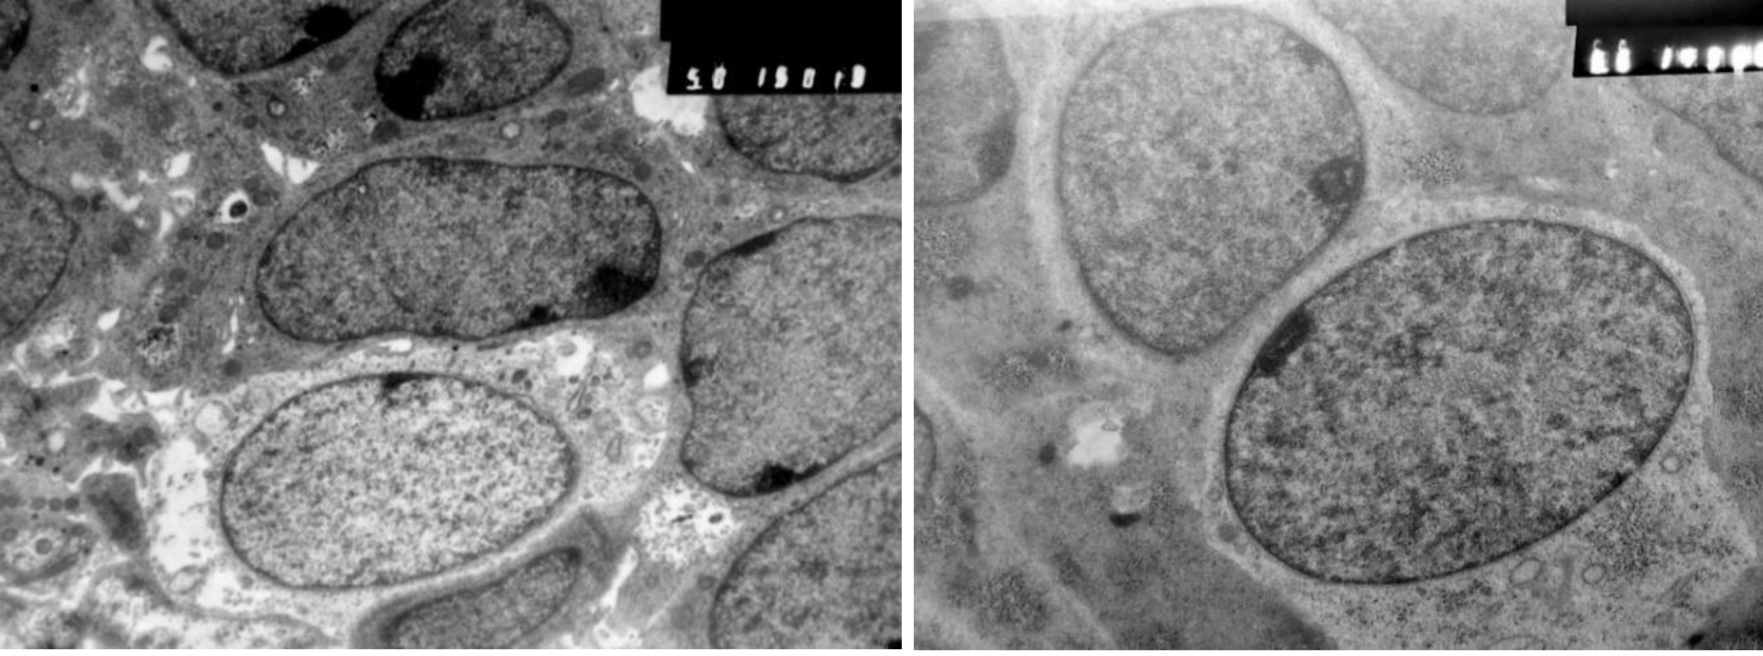

Эмбрионов человека (всего 127, не менее 4 на каждой СК) получали при проведении медицинских абортов по социальным показаниям у анамнестически здоровых женщин с их информированного согласия в ЛПУ г. Тюмени. Возраст зародыша определяли с учетом сведений акушерского анамнеза, ультразвукового исследования, морфометрии, визуального осмотра. Материал фиксировали в 10%-м нейтральном формалине, заливали в парафин. Срезы окрашивали гематоксилином Майера и эозином, ШИК-методом по Мак-Манусу. Для электронно-микроскопического исследования материал фиксировали в 5%-м растворе параформальдегид-глутаральдегидной смести, дофиксировали в 1%-м растворе OsO4 при температуре +4 °С, заливали в аралдит. Срезы контрастировали уранил-ацетатом. Электроннограммы готовили на электронном микроскопе JEM-1011 (JEOL, Япония) в Сибирском отделении РАН г. Тюмени.

Карман Сесселя в гистологическом препарате ограничивает нарастающий пласт многослойного эпителия, который смещается с задней стенки КР на дорзальную стенку глоточной кишки. Перемещение многорядного эпителия по градиенту роста КР сопровождается активизацией апоптоза, пролиферацией клеток в составе пласта и мезенхиме, а также формированием эпителиоцитов качественно новой генерации, потерявших связь с базальной пластинкой эпителия и участвующих в восполнении дефектов в нишах апоптоза (рис. 4).

Начиная с 15 СК в эпителии КР выявляются мерцательные клетки и макрофаги моноцитарного генеза. Эпителий преобразуется в полидифферонную структуру. В составе выстилки передней, а затем дна и задней стенки КР, начиная с 19 СК, выявляются дифференцирующиеся аденоциты и аденотропоциты (рис. 5).